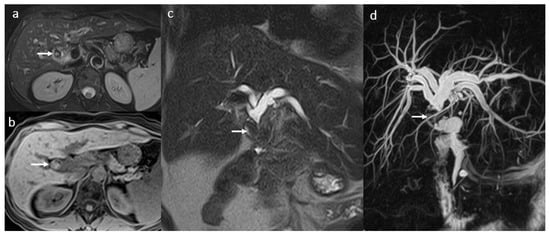

3.4. Biliary Anastomotic Stricture

3.5. Biloma and Bile Leaks